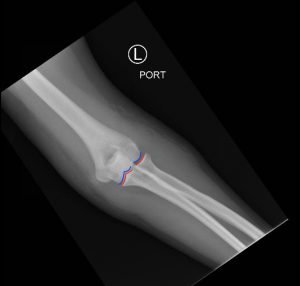

Posterior Elbow Dislocation, AP XRay, reduced, Annotated. JETem 2016

Posterior Elbow Dislocation